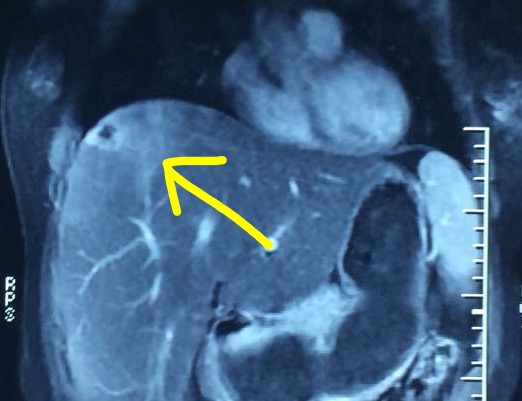

治疗前磁共振